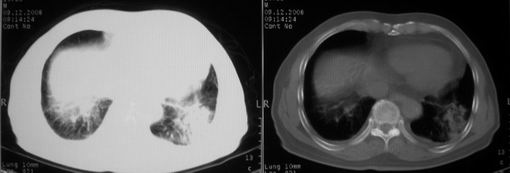

男,78岁,咳嗽、咳痰、发热入院,抗炎治疗一周后已退热,咳血似痰。

10月9日片:

ct左肺下叶大片状高密度影,病变密度不均,界限不清,左侧胸腔积液,治疗后复查临床症状好转而影像学表现病变有发展,还是首先考虑感染性病变,复查时间短附合感染性病变的病理改变。

两肺炎症感染(以左肺下叶为著),双侧少量胸腔积液;建议继续抗炎治疗。